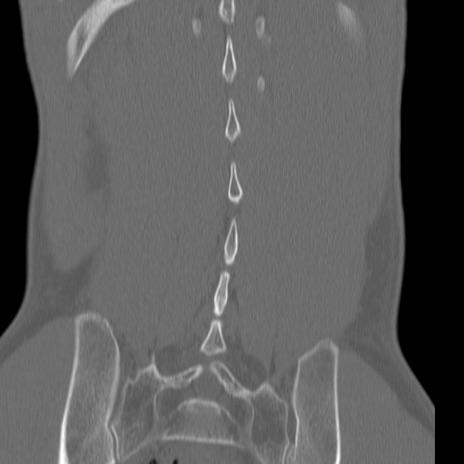

腰椎CT

3D再構成